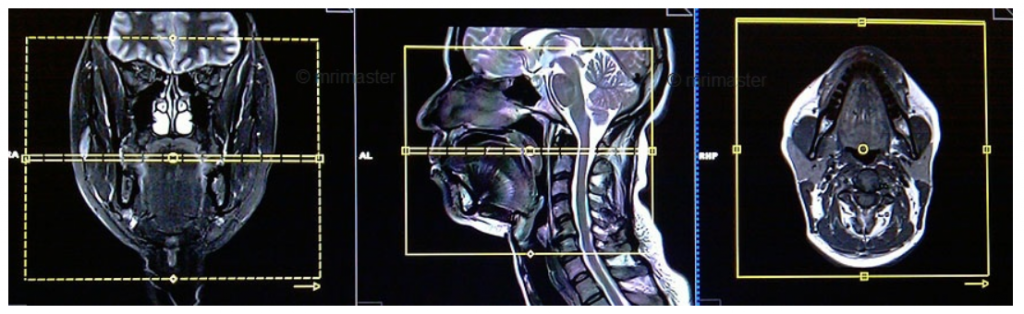

Cộng hưởng từ vùng mặt-cổ sử dụng một từ trường mạnh, các sóng radio và máy vi tính để cho ra những hình ảnh chi tiết của các cấu trúc vùng mặt-cổ rõ ràng hơn và chi tiết hơn các phương tiện hình ảnh khác. Cộng hưởng từ không sử dụng tia bức xạ ion hóa và có thể cần tiêm thuốc tương phản gọi là gadiolinium, thuốc tương phản này ít gây Dị ứng hơn thuốc tương phản iodine.

- Đối với chụp cộng hưởng từ vùng mặt - cổ, thiết bị sẽ được đặt quanh cổ và đầu.